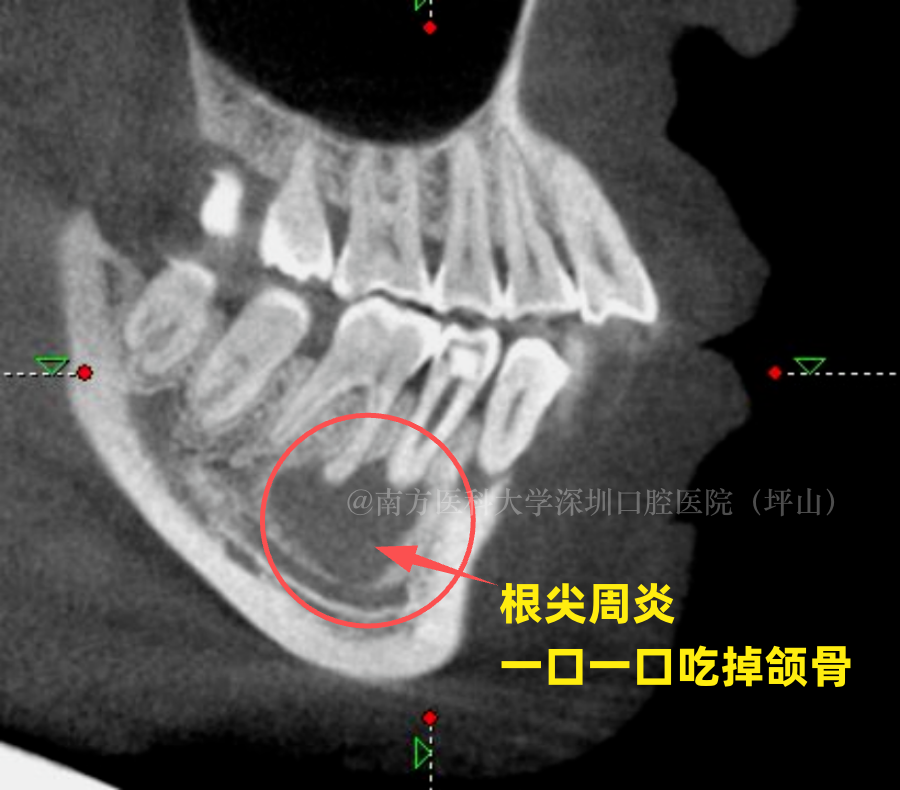

当牙髓炎发展到了根尖周炎这个阶段,牙髓组织完全坏死了,细菌从根尖孔进入到我们周边的组织,然后突破了牙槽骨粘膜,破坏牙槽骨,形成比较明显的一些病变,处理起来就更复杂了。

在这个阶段,因为牙神经已经坏死,患牙不会对冷热刺激敏感,但是咬东西的时候会疼。因为在根尖的部位出现了炎症,有一些脓液积聚在这个根尖部分,然后形成肿胀、疼痛。当它肿胀到一定程度,会在牙龈上形成瘘口排脓。

如果脓液长期压迫颌骨,形成了囊肿,不及时治疗的话,囊肿会越长越大,侵蚀骨头形很大的空腔,最后这个牙也只能拔掉。